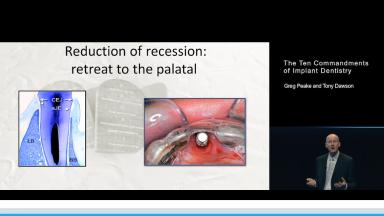

A similar set of rules might also be espoused for implant dentistry. In this presentation, Greg Peake (Periodontist) and Tony Dawson (Prosthodontist) bring a somewhat confronting, occasionally irreverent, and often humorous approach to this topic.

They discuss factors that have the potential to affect the success of implant treatments, and suggest a set of rules that might help us all minimise the risks of complications in the treatments that we provide to our patients.